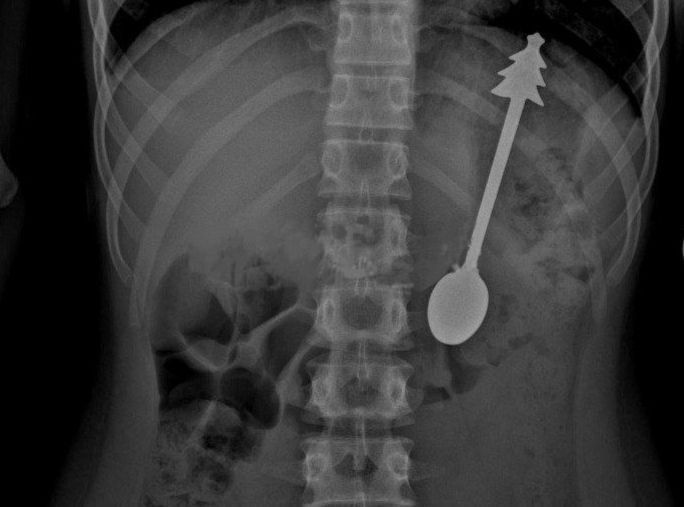

Его срочно доставили в больницу, где провели операцию по удалению столового прибора с елочкой на ручке. Все прошло успешно, и уже на следующий день ребенка отпустили домой, сообщили в местном минздраве.Подписаться...